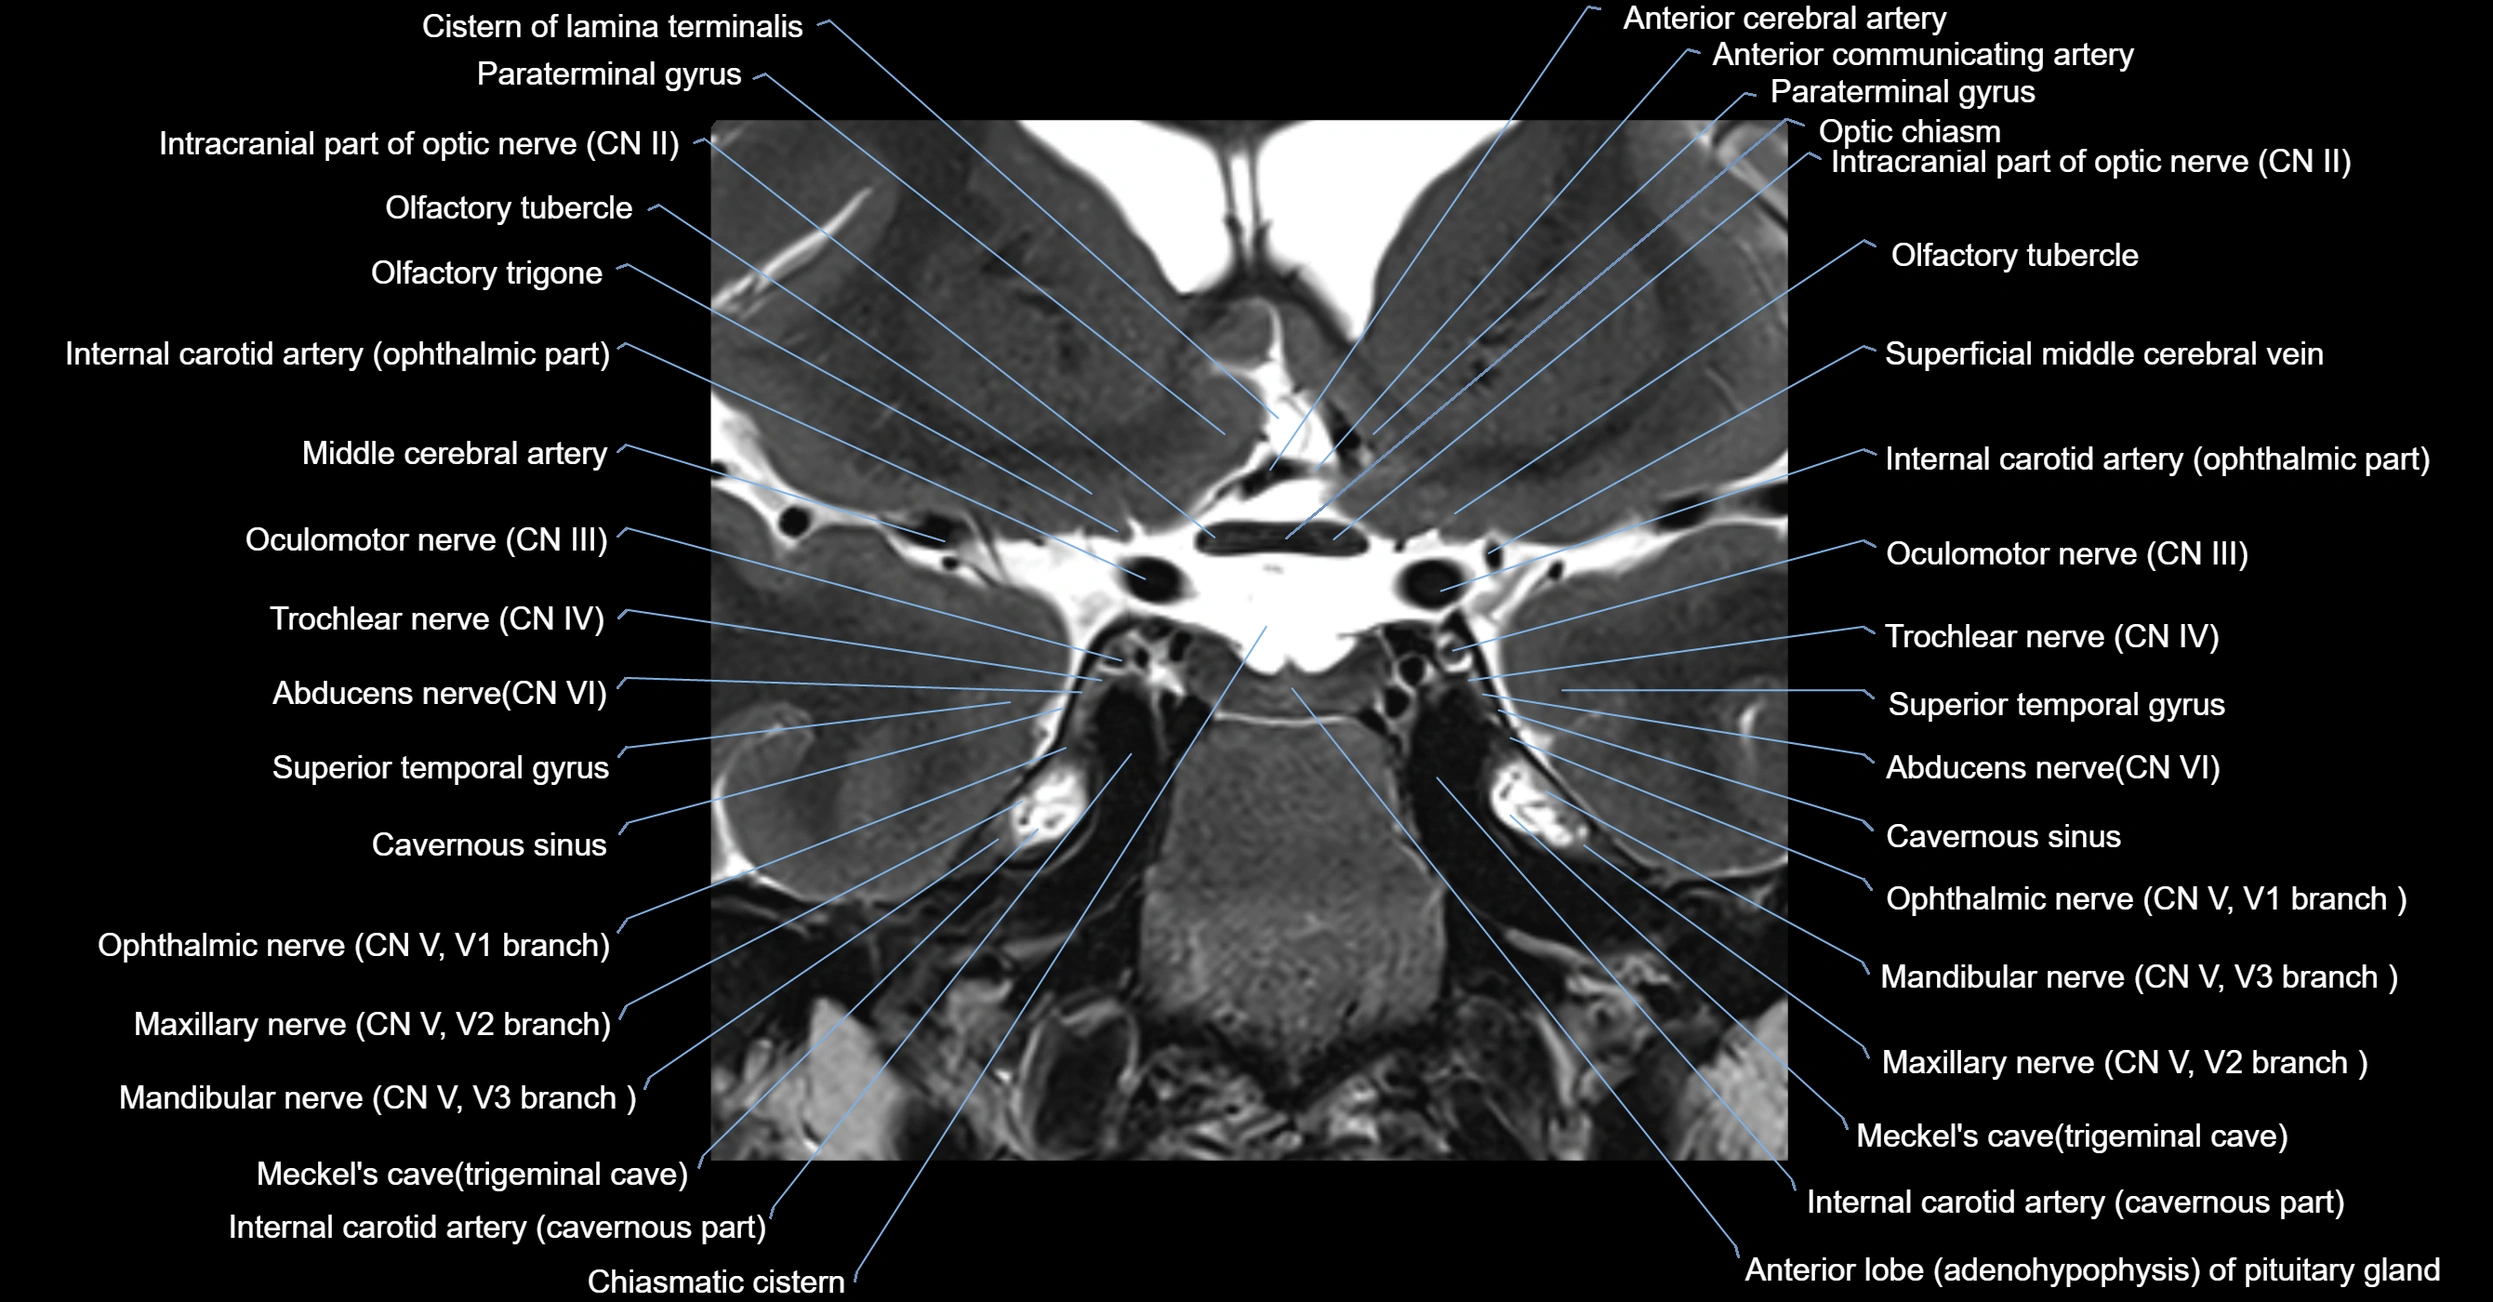

MRI Appearance

-

The abducens nerve is a small, thin, linear structure

Best visualized on high-resolution T2-weighted 3D MRI sequences (e.g., FIESTA or CISS)

Seen as a hypointense (dark) line running from the brainstem at the pontomedullary junction, traversing the prepontine cistern, and entering Dorello’s canal under the petrosphenoidal ligament, then into the cavernous sinus, and finally the orbit

May be challenging to visualize in standard MRI due to its small size

Pathology may be inferred by absence, displacement, or enhancement of the nerve

MRI images